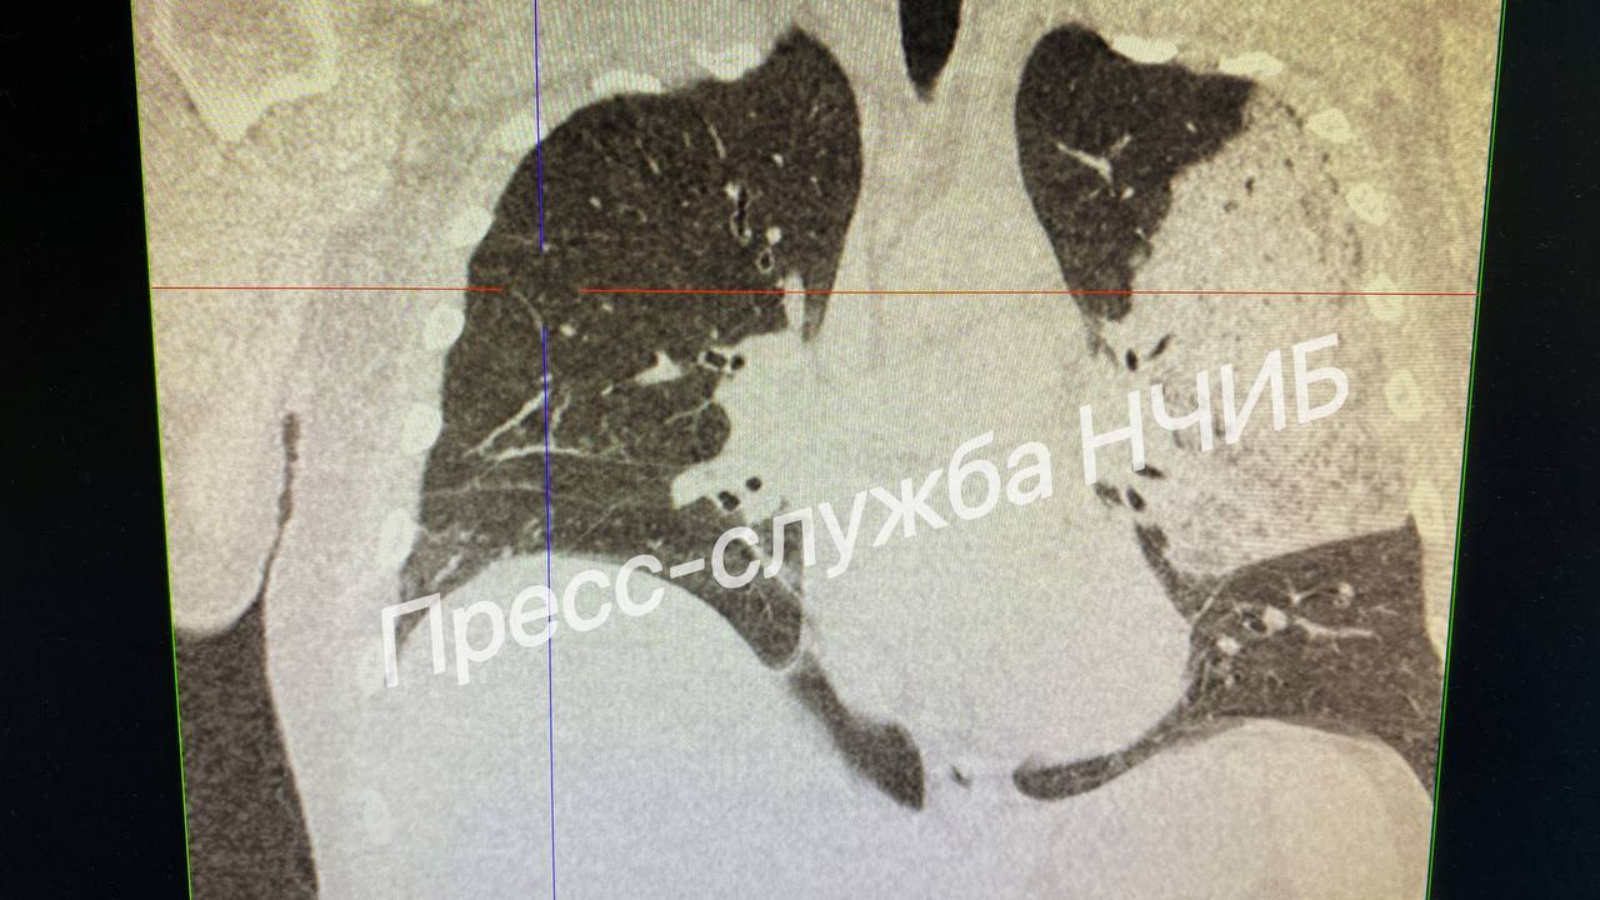

На снимке – легкие пациента, за чью жизнь боролись врачи. По словам Ришата Хакимова, заведующего ОРИТ инфекционной больницы, "Изначально мы не давали оптимистичных прогнозов".

51-летний мужчина поступил в инфекционную больницу с высокой температурой и изнуряющим кашлем. Компьютерная томография выявила обширное поражение легочной ткани. Это потребовало немедленной госпитализации в реанимацию.

Лишь спустя время на снимках стала выявляться положительная динамика. Пациент постепенно пришел в сознание, его удалось отключить от ИВЛ и перевести в палату.

«Он провел на ИВЛ 10 дней, – отмечает врач. – Изначально мы не давали оптимистичных прогнозов из-за тяжелой пневмонии, вызванной бактериальной инфекцией. Это стало возможным только благодаря интенсивной терапии».